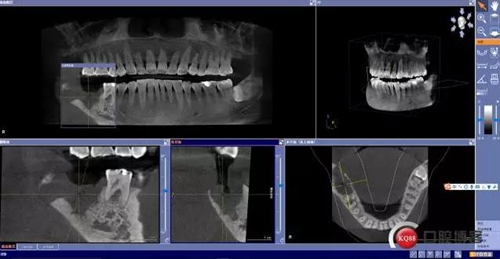

X線及CBCT檢查:47、48根尖周區(qū)大面積低密度影像,波及下牙槽神經(jīng)管,部分區(qū)域至神經(jīng)管以下。CBCT顯示神經(jīng)管走形于47根尖炎癥區(qū)下方(已侵犯)48炎癥區(qū)頰側(cè)(已侵犯)

術(shù)前CBCT分析

術(shù)后影像分析